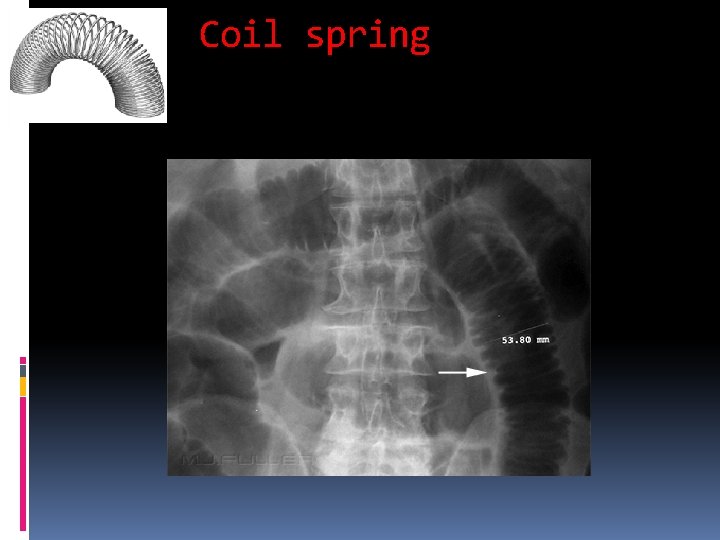

Coil spring

Mechanical LBO Colon dilates from point of obstruction backwards Little/no air fluid levels (colon reabsorbs water) Little or no air in rectum/sigmoid